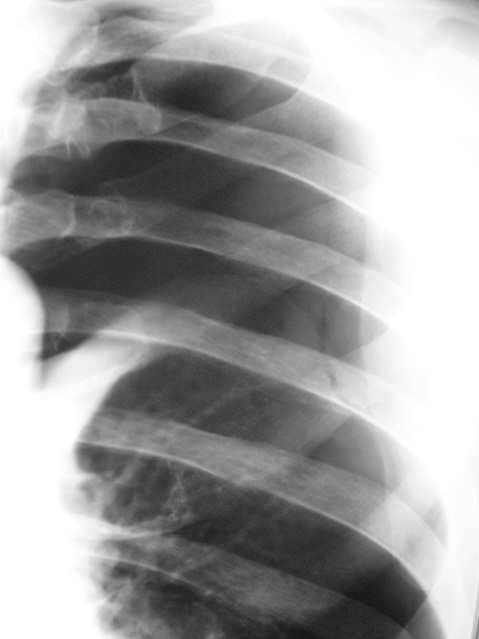

Спонтанный пневмоторакс справа. Правое легкое поджато на три четверти, хорошо виден его наружный край.